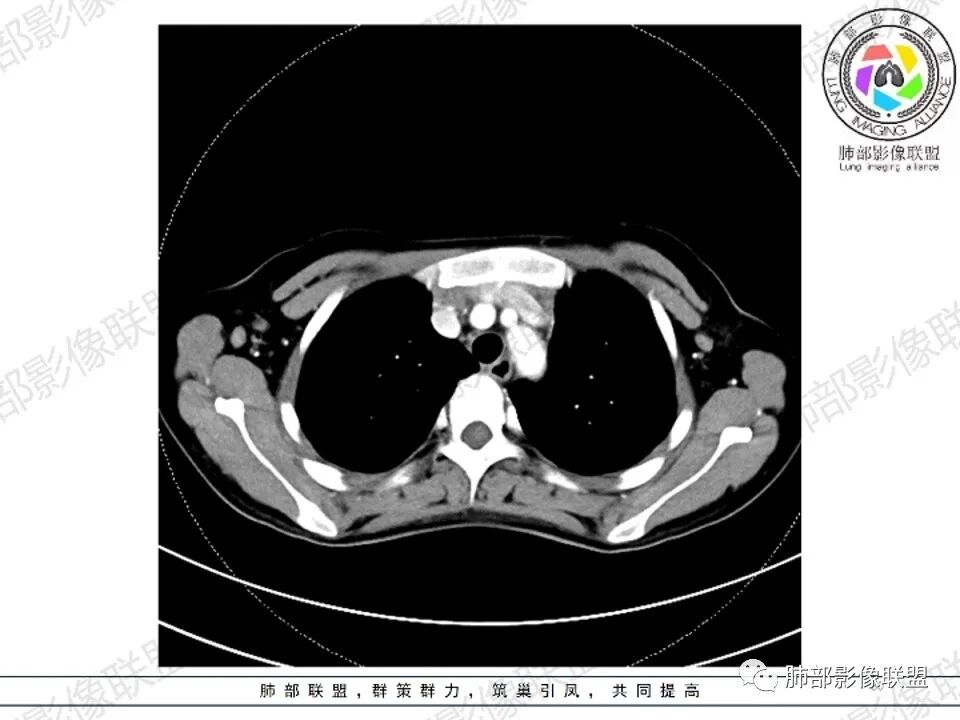

2.影像显示前纵隔不规则块状影,依势贴附心脏大血管旁,密度不均,边界不甚清楚,有结节融合感。

3.病灶轻度不均匀强化,可见血管穿行,散在液性低密度区。

双肺门未见肿大淋巴结。

4.双侧腋窝区见增大淋巴结,边界清楚。